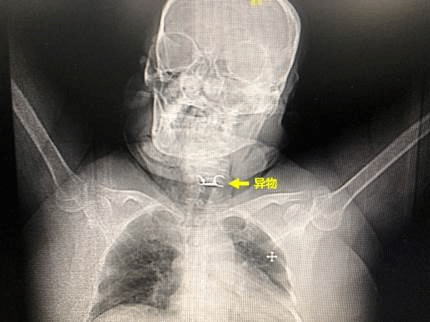

64岁的女性陈某,因误食异物(假牙)后喉部疼痛、呼吸困难,被120急救车紧急送往ac米兰官网中文网站一院急诊急救中心。胸外科常浩教授为患者检查发现异物形状特殊、位置刁钻,并且固定假牙的钢钩已刺破食管壁,引起纵隔感染,患者随时面临窒息风险。同时,钢钩毗邻左颈内动脉,随时有刺破颈部血管,导致大出血的风险,患者的生命悬于一线。

在医务科主任李峒作协调下,医院开辟绿色通道,紧急将患者收至外科缓冲病房,并完善相关检查。同时,胸外科常浩教授团队组织消化内科、耳鼻喉科、手术室、麻醉科等多个科室迅速行动,在门诊中心手术室联合制定了完备的手术方案和术中应急预案,随时可以为患者安全快速的取出异物。